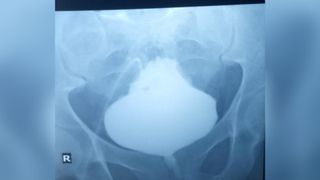

In an unusual case, a man's bladder swelled dramatically at its base, taking the shape of a Christmas tree.